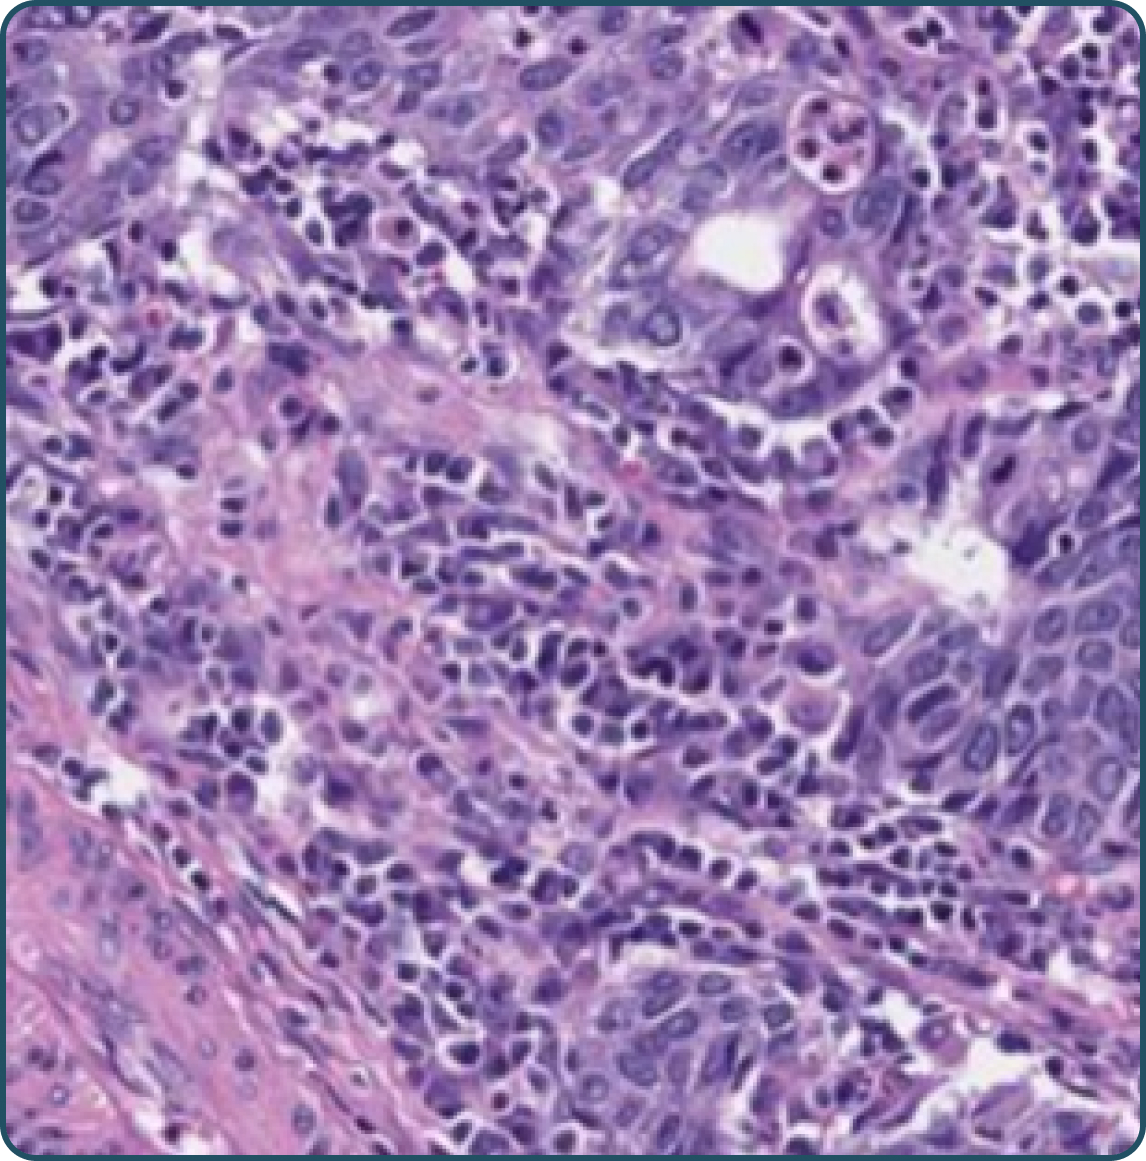

Tumor cells exhibiting moderate (2+) to strong (3+) membranous staining3-5

Any tumor cells with moderate (2+) to strong (3+) membranous staining, including any of the following:

No tumor cells with moderate (2+) to strong (3+) membranous staining OR tumor cells only exhibiting: